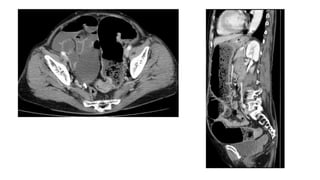

Scanner pelvien avec injection

Stercolithe

Infiltration de la graisse

Épaississement

Appendicite pelvienne en TDM